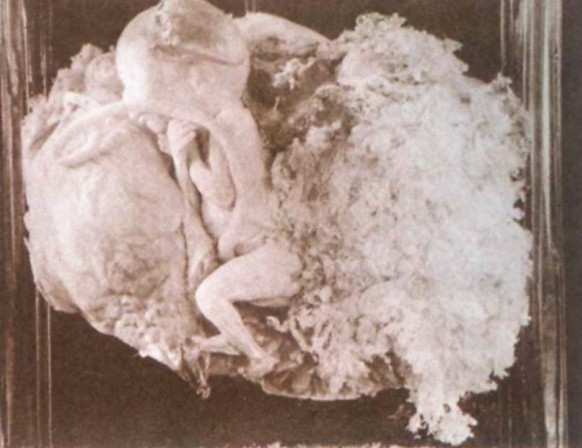

2.部分性葡萄胎 仅部分绒毛呈水泡状,合并胚胎或胎儿组织,胎儿多已死亡,且常伴发育迟缓或多发性畸形,合并足月儿极少。镜下见:①有胚胎或胎儿组织存在;②局限性滋养细胞增生;③绒毛大小及其水肿程度明显不ー;④毛呈显著的扇贝样轮廓、间质内可见滋养细胞包涵体;⑤种植部位滋养细胞呈局限和轻度的异型性。完全性葡萄胎和部分性葡萄胎的核型和病理特征鉴别要点见表28-1。

部分性葡萄胎大体观 部分性葡萄胎大体观 部分性葡萄胎镜下观(100×)

中期妊娠,胎儿合并水泡状胎块。见大小不一绒毛,滋养细胞轻度增生